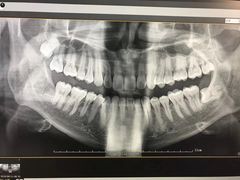

• 李桂凤口腔

• -李桂凤口腔